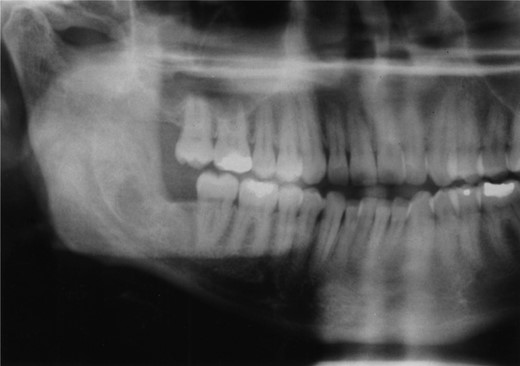

A 25-year-old man presented with a 2-month history of facial pain and limited mouth opening associated with a 3-week history of swelling of the right cheek. Radiographic analysis revealed a loculated, fluid-filled, well-demarcated lesion destroying and expanding the ascending ramus, extending out into the soft tissues, from the condyle down to the angle (Fig. 1).

A well-demarcated lesion extending out into the soft tissues from the ramus of the mandible.